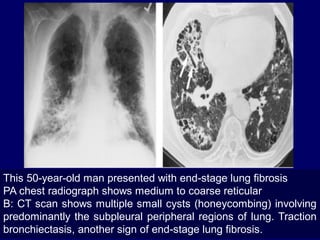

This 50-year-old man presented with end-stage lung fibrosis

PA chest radiograph shows medium to coarse reticular

B: CT scan shows multiple small cysts (honeycombing) involving

predominantly the subpleural peripheral regions of lung. Traction

bronchiectasis, another sign of end-stage lung fibrosis.